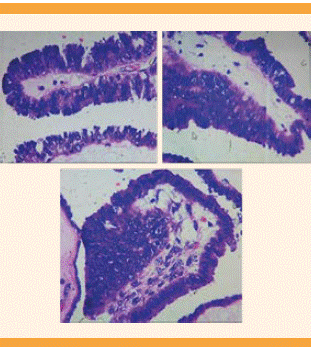

Figura 4 Microfotografía de TLO, con implantes en la cápsula sin datos de invasión por tumor seroso papilar.

Figura 5 Microfotografía de TLO seroso con formaciones micropapilares en forma de “medusa”, sin infiltración al estroma ovárico.